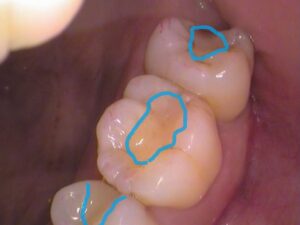

よく見てみると、

青枠の箇所に「レジン」というプラスティックの合成樹脂が詰められてあります。

白い材料なので一見分かりにくいですが、経年劣化による変色もあり、継ぎはぎみたいに歯に埋められています。

レントゲン(エックス線)検査で治療前に確認済みですが、このレジンの中で虫歯があります。